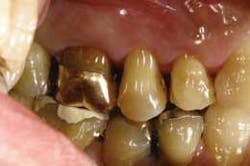

Wol-Ceram is now available from many national laboratories, and even if your local laboratory does not have Wol-Ceram, they can have the copings fabricated by one of the large laboratories. Wol-Ceram is the first all-ceramic system that allows you to prepare teeth with a featheredge margin; shoulders and chamfers are not required. Many dentists have complained about the extra preparation required for most all-ceramic restorations, feeling that a standard PFM preparation should be adequate reduction.

From the very first three units I cemented, I knew there was something special about the Wol-Ceram system. These were the first all-ceramic crowns I had ever inserted that felt like PFMs as they slid down into place. There is nothing quite so reassuring as being able to feel the mechanical retention of a crown as it moves down the prep.

I still prefer to cement rather than bond, and Wol-Ceram can be cemented with any crown and bridge cement of your choice. The next time you have a need for an all-ceramic crown that preps, fits, cements, and costs the same as a PFM, give Wol-Ceram a try.